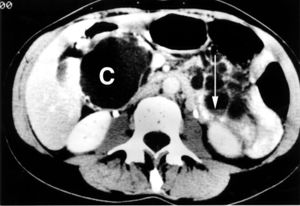

كيسة پنكرياس كبيرة عند الناتئ الشصي للپنكرياس.

الكيسة الپنكرياسية pancreatic cyst، هي جيوب كيسية من السوائل على الپنكرياس أو داخلها. الپنكرياس عضو كبير يقع خلف المعدة ينتج الهرمونات والإنزيمات التي تساعد على هضم الطعام.

معظم تكيسات الپنكرياس غير سرطانية، ولا يسبب العديد منها أي أعراض. يتم اكتشافها في أثناء الفحص بسبب مشاكل أخرى. بعضهم جيوب غير سرطانية (حميدة) من السوائل بها ندوب أو أنسجة ملتهبة، وليست من نفس نوع الخلايا الموجودة بالتكيسات الحقيقية (الكيسة الكاذبة).[1]